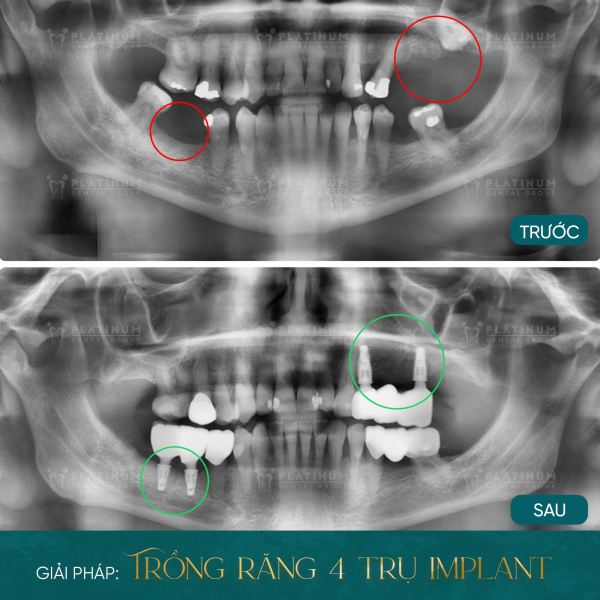

Hành trình lấp đầy khoảng trống nụ cười của MR. Raymond Boost

Mr. Raymond Boost – vị khách đến từ Úc đã từng phải sống trong nhiều năm với tình trạng mất gần như toàn bộ răng hàm. Việc ăn uống trở nên khó khăn khi ông chỉ còn vài chiếc răng cửa để đảm nhiệm chức năng nhai. Những ảnh hưởng kéo dài khiến sức khỏe răng miệng và chất lượng sống suy giảm nghiêm trọng:

- Không thể ăn uống thoải mái như trước do khả năng nhai bị hạn chế

- Răng cửa bị mòn nhanh vì phải chịu lực nhai quá lớn

- Xương hàm tiêu dần theo thời gian tại những vị trí mất răng

- Các răng còn lại yếu đi, sậm màu và có dấu hiệu viêm nhiễm

Sau quá trình thăm khám và tư vấn chuyên sâu tại Platinum Dental Group, ông Raymond đã quyết định lựa chọn giải pháp trồng 4 trụ Implant phục hình toàn bộ hàm răng đã mất. Kết quả mang lại không chỉ là một hàm răng chắc khỏe mà còn là sự tự tin, niềm vui ăn uống và tận hưởng trọn vẹn từng khoảnh khắc cuộc sống.